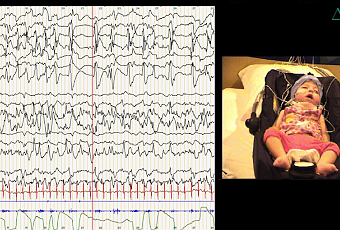

Les épilepsies néonatales peuvent affecter sévèrement le développement cognitif et sont souvent pharmaco-résistantes. Dans une famille avec une épilepsie partielle migrante, nous avons identifié des mutations dans le gène TBC1D24 chez les enfants atteints (mutations récessives héritées des parents non atteints) par séquençage d'exome (...). Inserm, Aix-Marseille Université, France

26 familles ont été incluses dans cette étude. Nous avons effectué un séquençage d’exome dans les 17 première familles recrutées ; et avons recherché TBC1D24 par séquençage par technique de Sanger dans les familles suivantes. Nous avons identifié des mutations du gène TBC1D24 chez 11 sujets provenant de neuf familles (par séquençage d’exome dans sept familles et séquençage Sanger dans deux familles). 18 familles comprenaient des sujets porteurs des cinq caractéristiques principales du syndrome DOORS, des mutations TBC1D24 ont été identifiées dans la moitié de ces familles. Les crises (d'épilepsie) présentées par les sujets porteurs incluaient crises tonico-cloniques généralisées ; et des spasmes complexes partiels, focaux cloniques et infantiles. Des 18 individus atteints du syndrome DOORS, issus de 17 familles sans mutations TBC1D24, huit n’ont pas eu de crises et trois n’étaient pas atteints de surdité. Dans les études d’expression génique, quelques mutations ont altéré la stabilité de l’ARNm TBC1D24. Nous avons aussi détecté l’expression de Tbc1d24 dans les chondrocytes des phalanges et le condyle mandibulaire de souris, ce qui suggère un rôle de TBC1D24 dans la génèse du squelette.